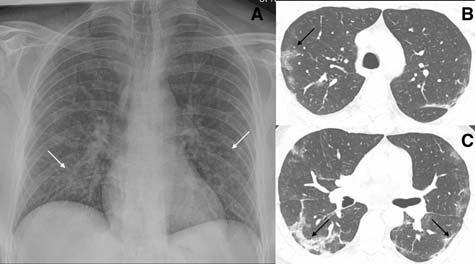

Distribution :

Classical distribution seen in most of the patients is that of bilateral involvement with lower lobe predominance. Peripheral distribution was more common than central involvement12,13,17 (Fig 4). In a more recent study by Weinstock et al15, lower lobe predominance and peripheral distribution was seen in about 35% of patients but bilateral involvement was only seen in 21% of cases. Diffuse distribution of lung opacities can also be seen as the disease progresses. The appearances are similar to Acute Respiratory Disease Syndrome (ARDS) patterns10 (Fig 5).

4 — CXR of a 71-year-old man with 4 days history of shortness of breath. Classical features of hazy opacities are seen in the lower lobes bilaterally in a peripheral distribution. Image reproduced with permission from Covid-19 Database of the Fleischner Society.

Fig 7 — Atypical presentation of COVID-19 in the form of nodules (arrows) seen on the CXR (A) and the corresponding CT (B). Image reproduced with permission from Covid-19 Database of the Fleischner Society.